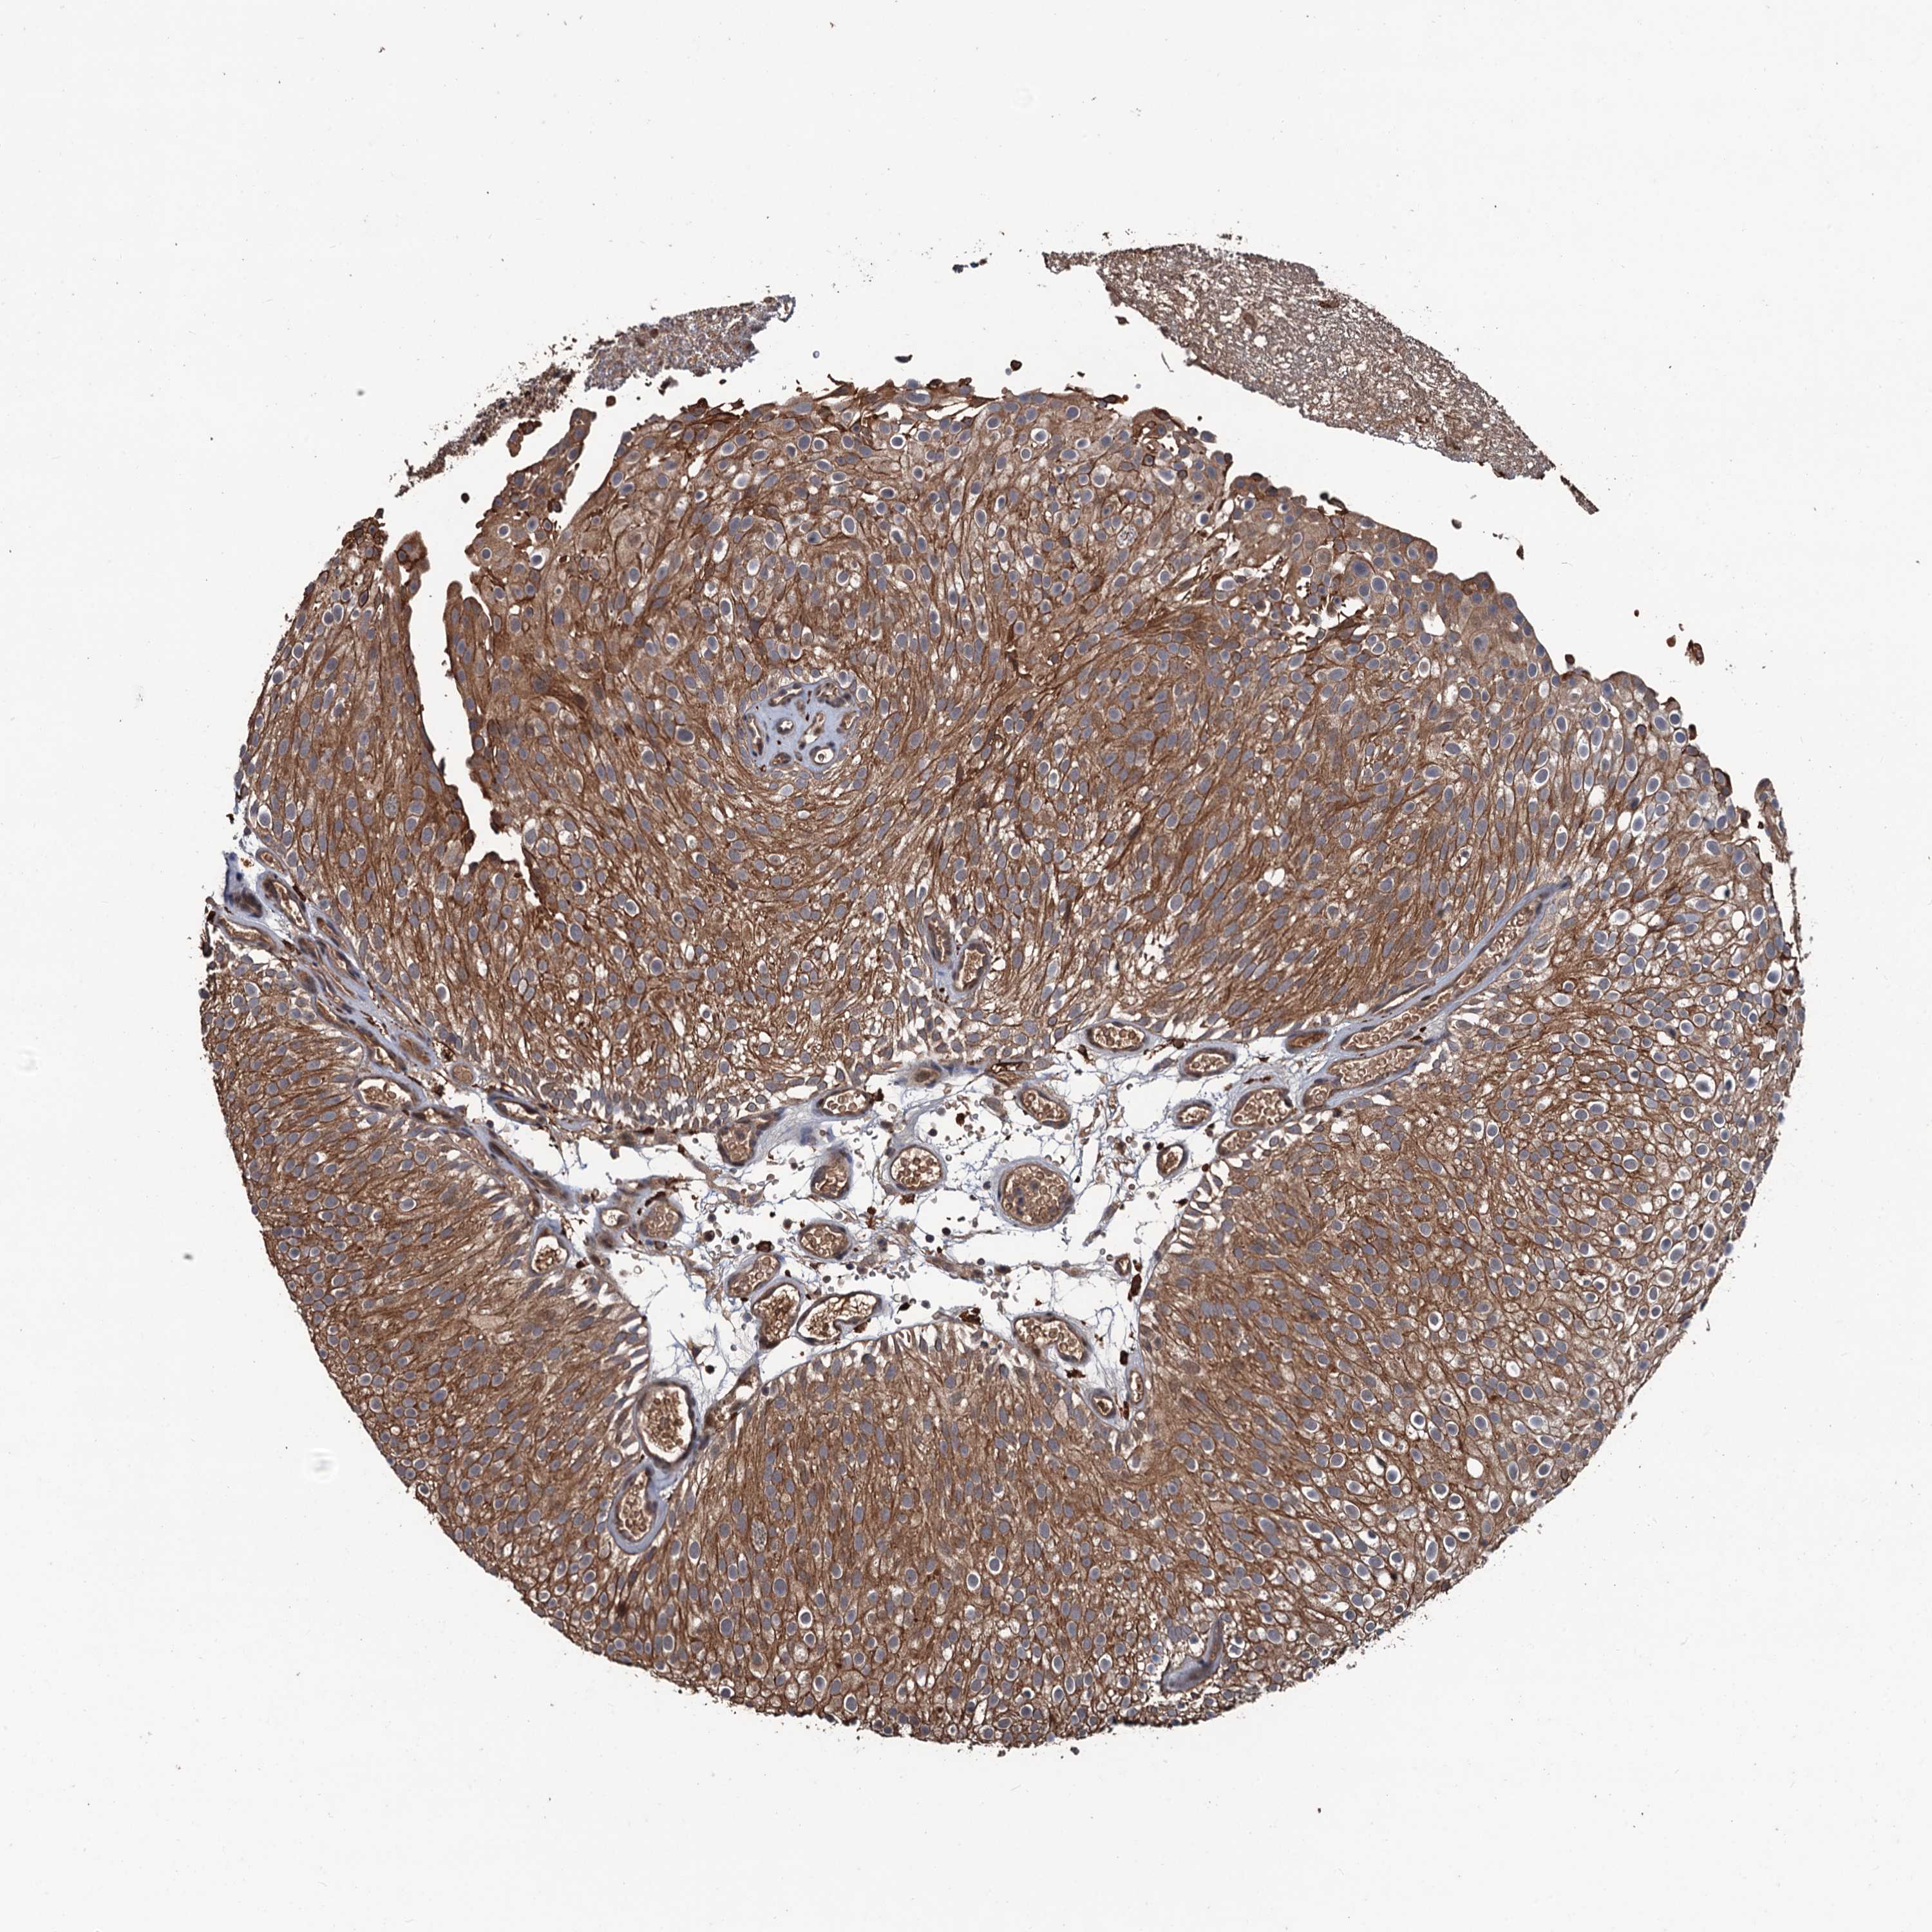

UROTHELIAL CANCER - Protein expressioni

A mouse-over function shows sample information and annotation data. Click on an image to view it in a full screen mode. Samples can be filtered based on level of antibody staining by selecting one or several of the following categories: high, medium, low and not detected. The assay and annotation is described here.

Note that samples used for immunohistochemistry by the Human Protein Atlas do not correspond to samples in the TCGA dataset.

Antibody stainingi

Antibody staining in the annotated cell types in the current human tissue is reported as not detected, low, medium, or high, based on conventional immunohistochemistry profiling in selected tissues. This score is based on the combination of the staining intensity and fraction of stained cells.

Each image is clickable and will lead to virtual microscopy that enables deeper exploration of all samples and also displays staining intensity scores, fraction scores and subcellular localization as well as patient and tissue information for each sample.

Antibody HPA039843

Staining

High

Medium

Low

Not detected

Intensity

Strong

Moderate

Weak

Negative

Quantity

>75%

75%-25%

<25%

None

Location

Nuclear

Cytoplasmic/membranous

Cytoplasmic/membranous,nuclear

Urothelial carcinoma, High grade

Urothelial carcinoma, Low grade